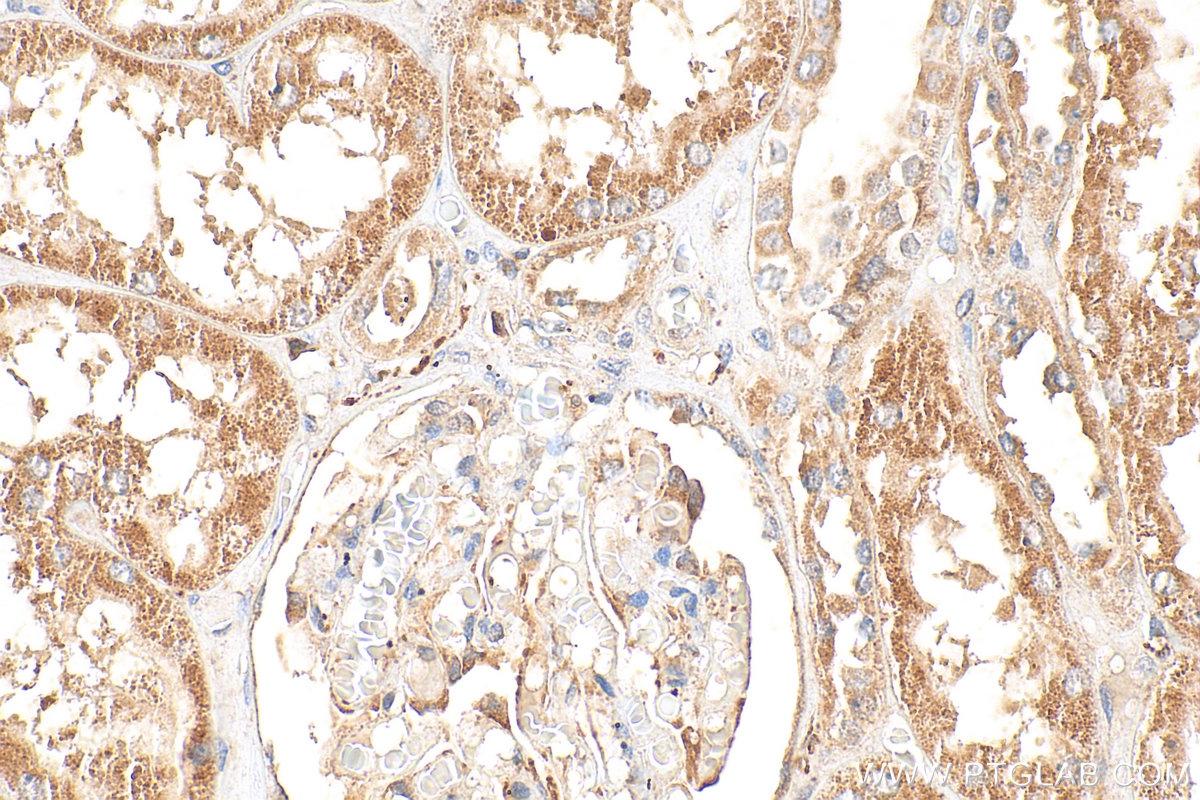

| Positive IHC detected in | human ovary cancer tissue, human kidney tissue Note: suggested antigen retrieval with TE buffer pH 9.0; (*) Alternatively, antigen retrieval may be performed with citrate buffer pH 6.0 |

| Immunohistochemistry (IHC) | IHC : 1:50-1:500 |

30215-1-AP targets TBXAS1 in WB, IHC, ELISA applications and shows reactivity with human samples.